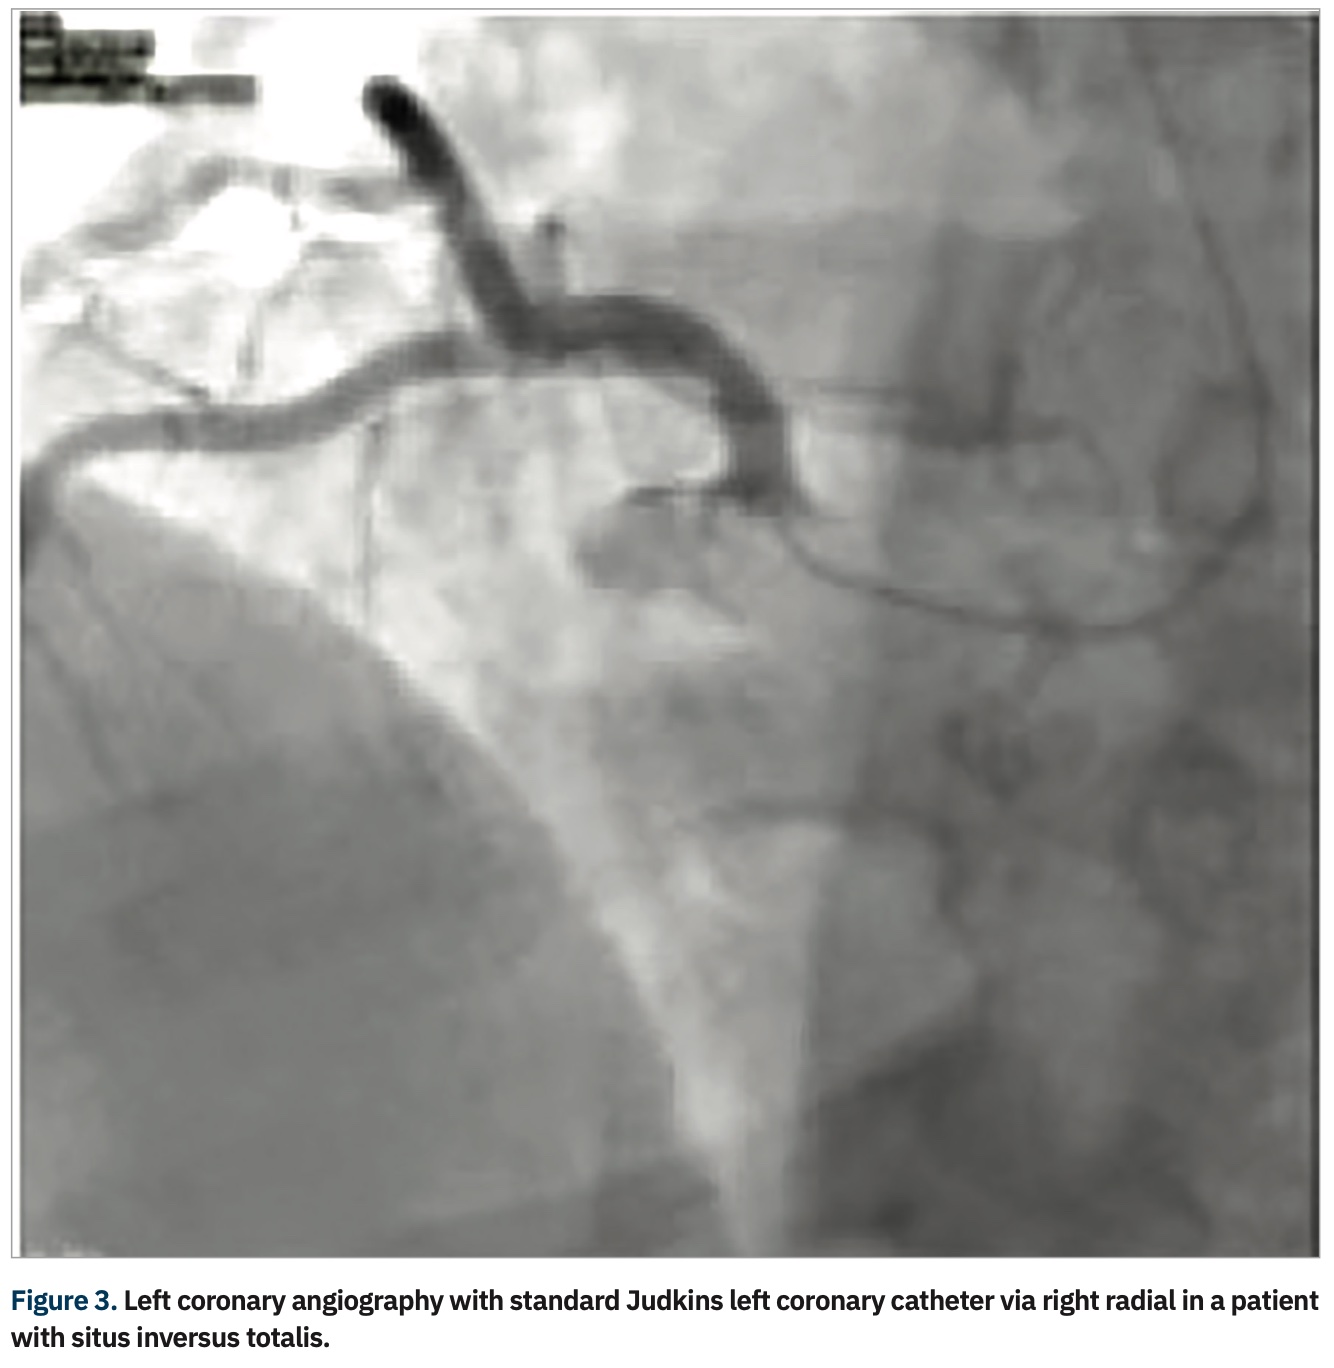

A review of 2100 failed transradial approaches for PCI found age >75 years (P<.001); prior coronary bypass surgery (CABG) (P<.001), and height <5 feet, 5 inches (165 cm) (P=.02) as independent predictors.9 Another study examined 1609 patients and found previous CABG, cardiogenic shock, and female sex as multivariable predictors for transradial failure of PCI (with right radial the default for transradial procedures, except in the case of prior CABG).10 Although a more experienced radial operator will often overcome the challenges of a right radial approach, there are still some patients where the majority of operators favor femoral access, such as patients with history of CABG. In a subgroup of patients (Table 1), access via the left radial artery may allow programs to “stay radial”. The catheter passing via the left arm follows a similar path as the femoral approach, with only one area of resistance in its path, at the left subclavian-aorta junction; conversely, the catheter passing via the right arm has two areas of resistance in its path, at the subclavian-brachiocephalic and the brachiocephalic–aortic junctions (Figure 2).11 An example of the analogy is the ease of right radial in those with situs inversus totalis (Figure 3), where with only one spot of resistance, the typical femoral catheters can be used easily via the right wrist.12